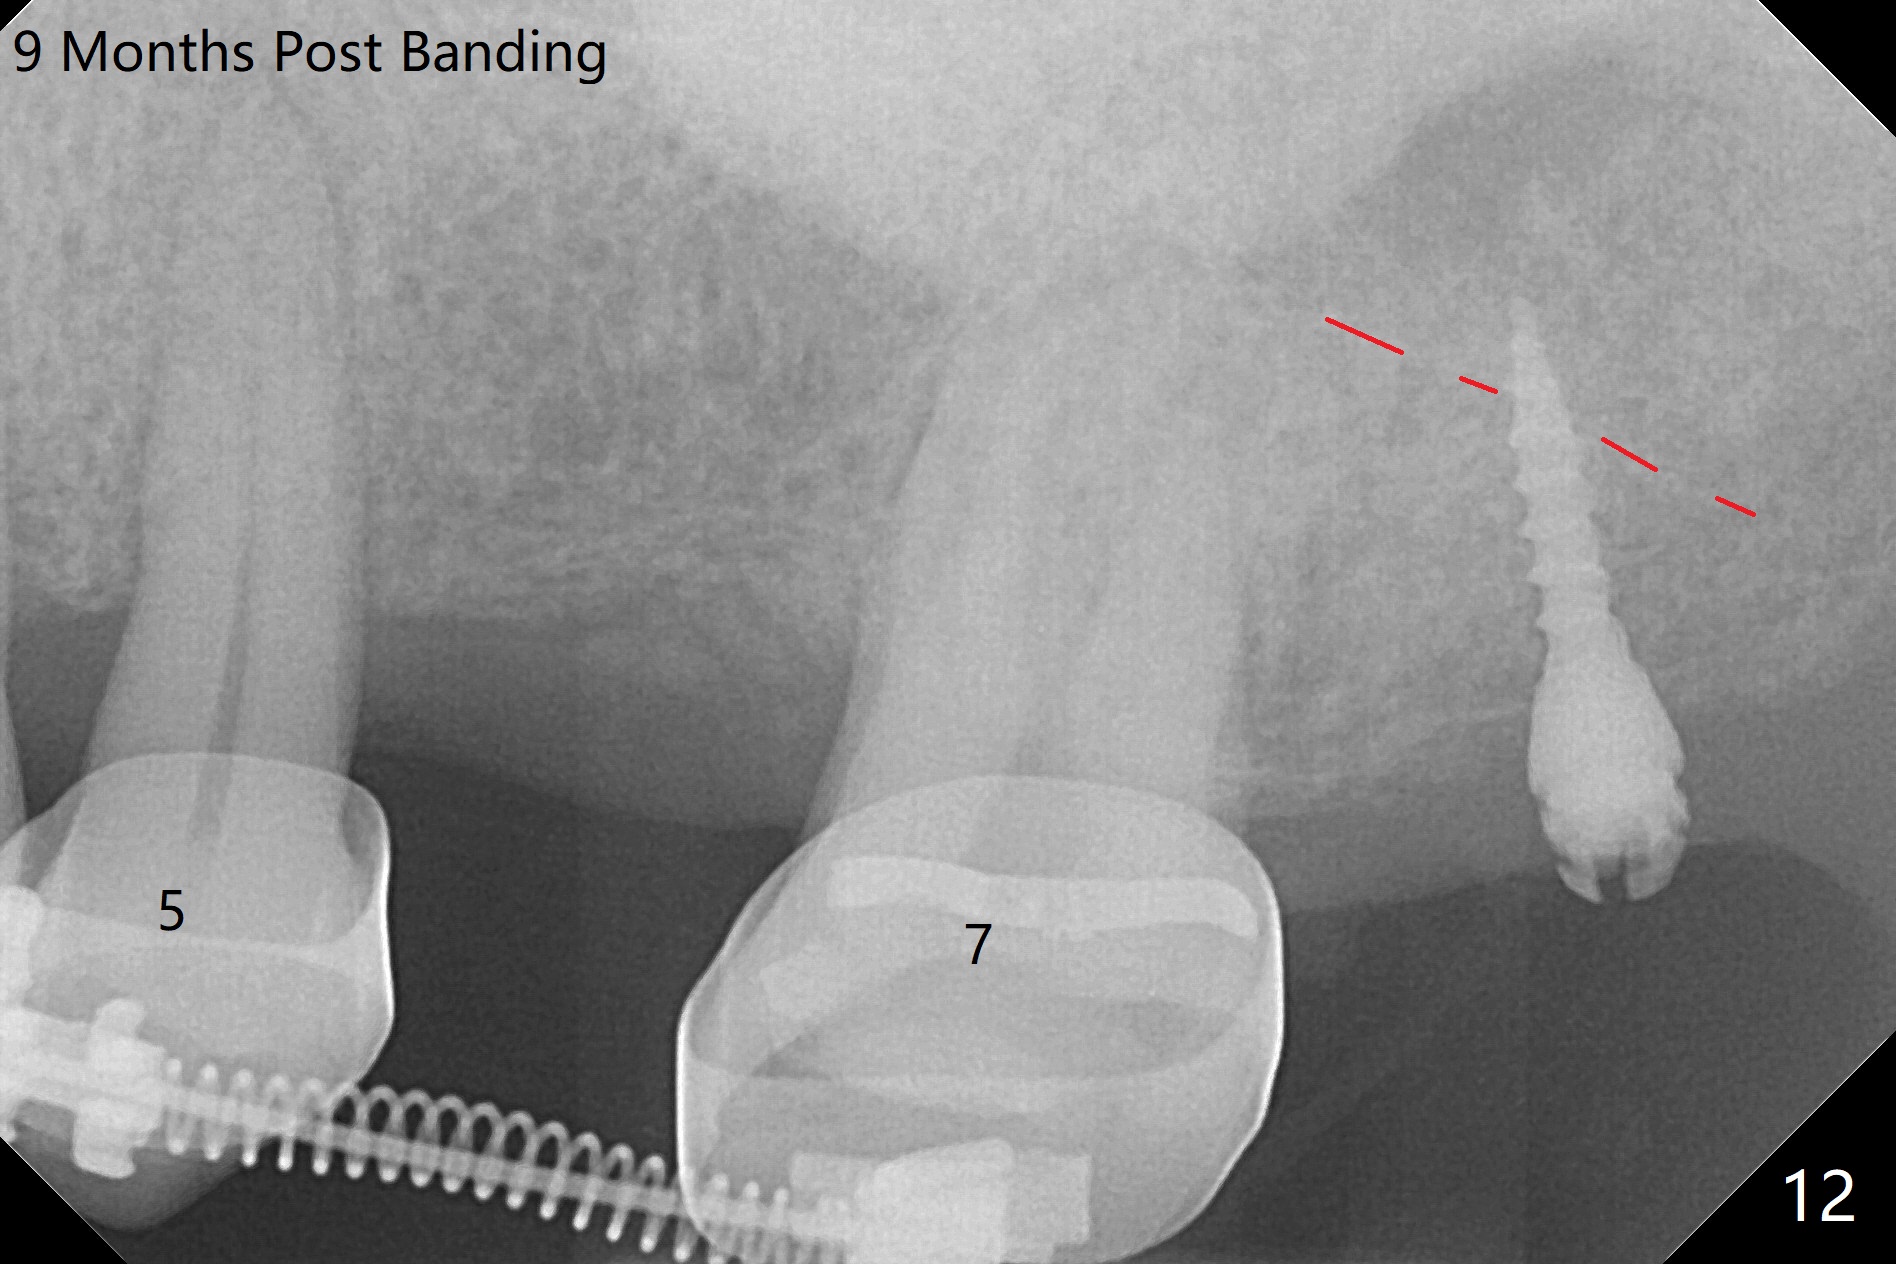

为了在左上6,左下7种植,使用右上3至左上5作为支抗推左上7远中,但是六个月效果不显著(图一),CT显示阻生牙(图一,二:8)没有阻挡。7远中植入1.6x8毫米微型植体,不过接近7根尖(图三),微型植体应该改变角度,而且往远中颊侧移位。最后效果不错(图四),植体马上启用(图五),而且同时取模做左下7导板。在微型植体牵引下,左上7的确往远中移位(图六,与图四对比),但是植体松动,马上植入3x10(2)毫米一段式植体,由于8阻挡,后者没有完全就位,稳定性差,没有启动。几天后也脱落。病人急着完成治疗,因为咀嚼困难。补救方法便是拔除阻生牙9(图七:x),让植体完全就位。切开后发现牙槽嵴处严重骨质吸收缺损(图八:D),离7很近,不适合种植。拔除8后(图九:S(socket)),两处植骨(粘性,图十),覆盖PRF膜,缝合。矫正九个月6空间相当双尖牙(图十二),还想增加2毫米才种植,病人急于完成治疗,所以再次植入微型植体,不同之处是切开,发现7远中颊侧骨质密度低(用探针),因此微型植体在腭侧植入(图十一:P),扭力似乎高,1.6x8毫米植体仿佛植入8牙槽窝(图十二:红虚线)。微型植体牵引一个月,磨牙缺牙间隙大约前磨牙大小,准备在远中(图十三)植入直径小植体(图十四),当后者整合时,用它继续推7。